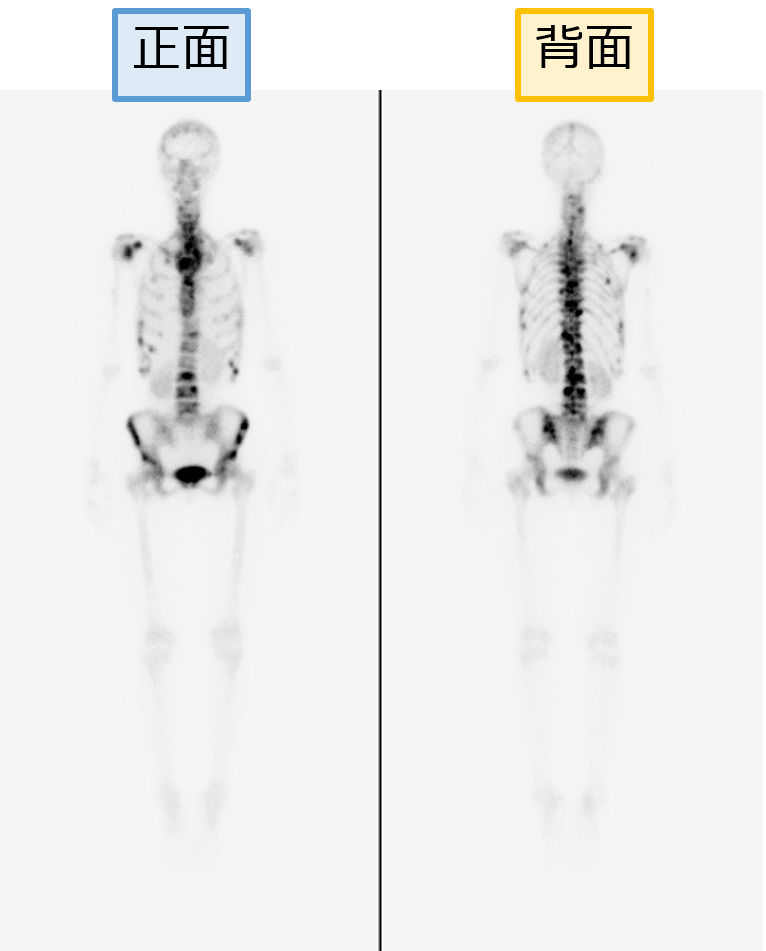

●骨シンチグラフィ

骨シンチグラフィ検査は、がんが骨へ転移しているかどうかを検出するのに頻繁に利用されますが、がんが骨に転移しているかどうかは、がんの治療を進めていくうえで重要な情報となります。

⇩拡大